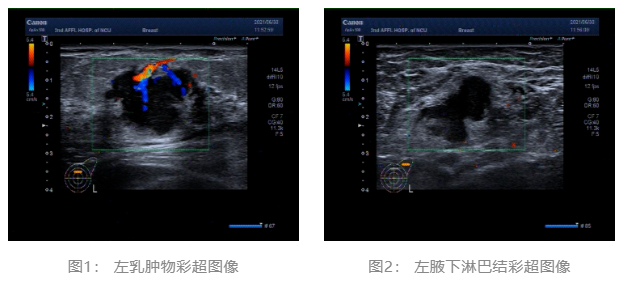

2021.06.30 乳腺彩超:左侧乳腺低回声团块,BI-RADS-US 4c类。左侧腋窝肿大淋巴结。(图1、2)

乳腺彩超: